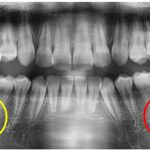

その日のレントゲン写真がこちら。

赤丸がついているところが中心結節が折れた歯の根っこの先です。

黄色丸のついた反対側の歯の根っこの先と比べて、赤丸の方には影があるのが分かります。

中心結節が折れて、歯の神経が口の中に出てしまった結果、神経の管から根っこの先まで細菌に感染してしまったのです。